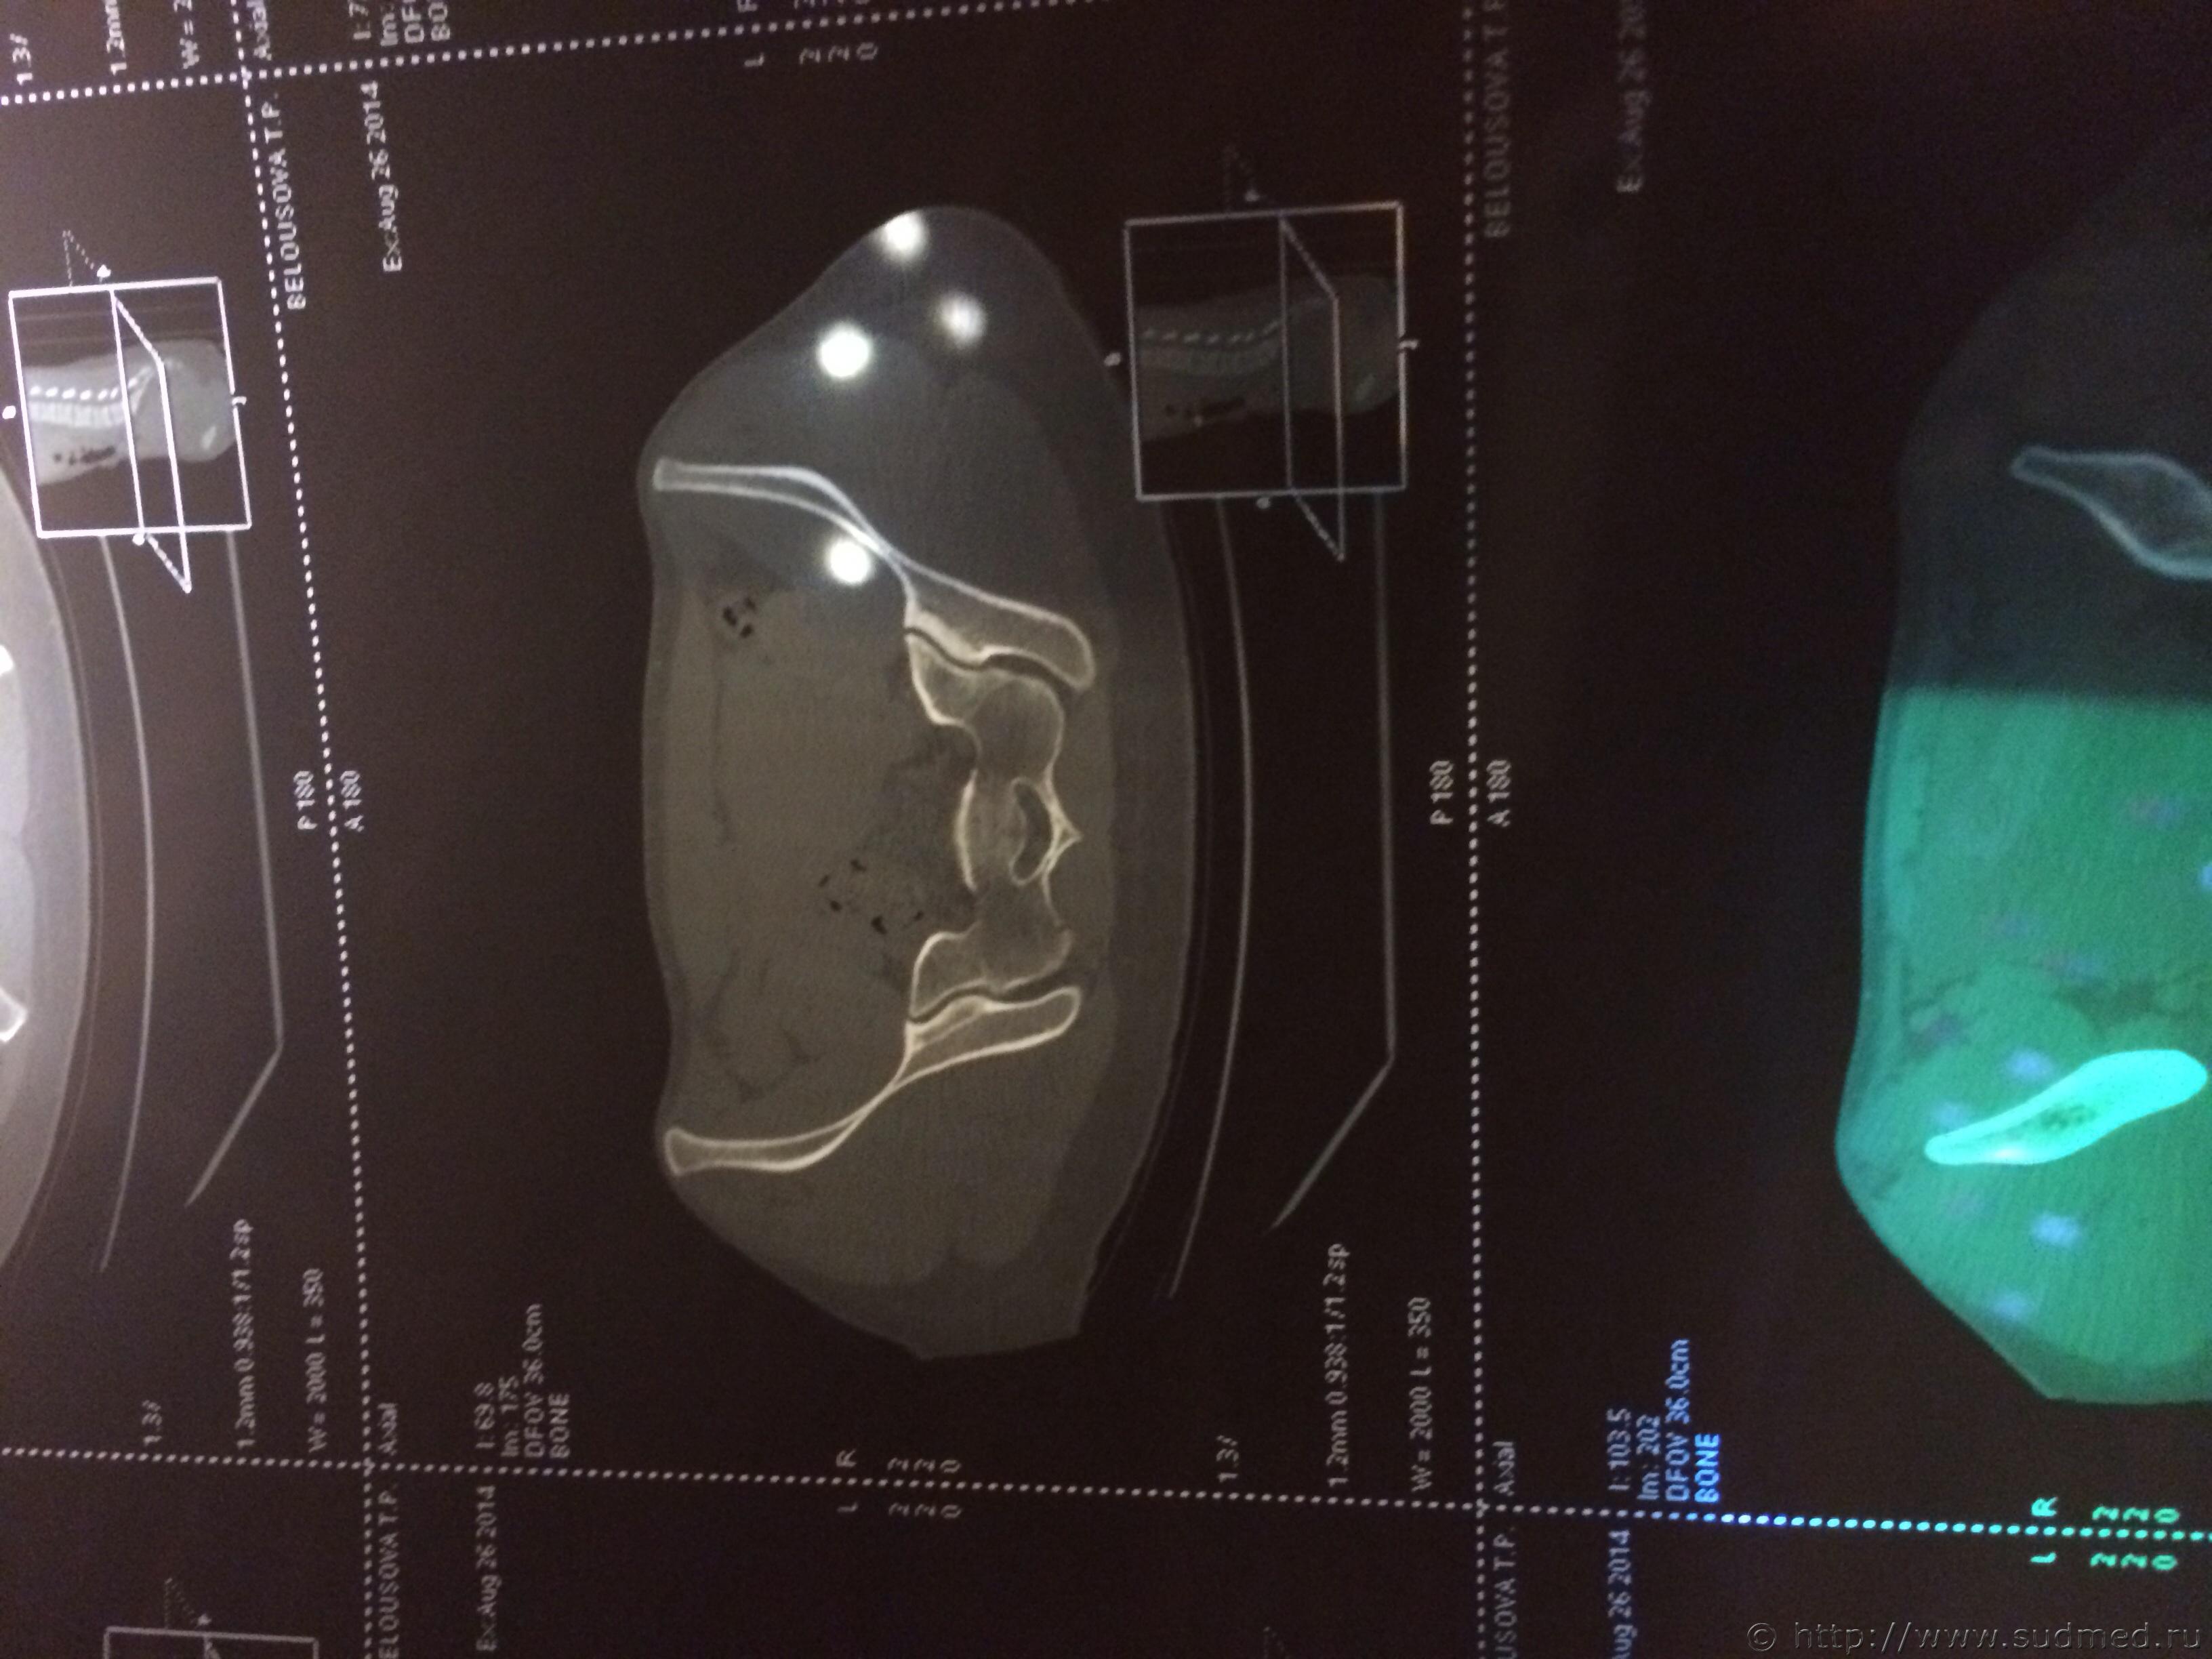

Спасибо! У меня результаты КТ, ошиблась)

КТ

Как мне видится - вертикальный перелом крестца. Тяжкий вред.

Впрочем, оставляю небольшую вероятность, что я не видел все сканы, да и качество их здесь, разумеется, хуже, чем изображение на пленке или на экране компьютера у врача, работающего на томографе.